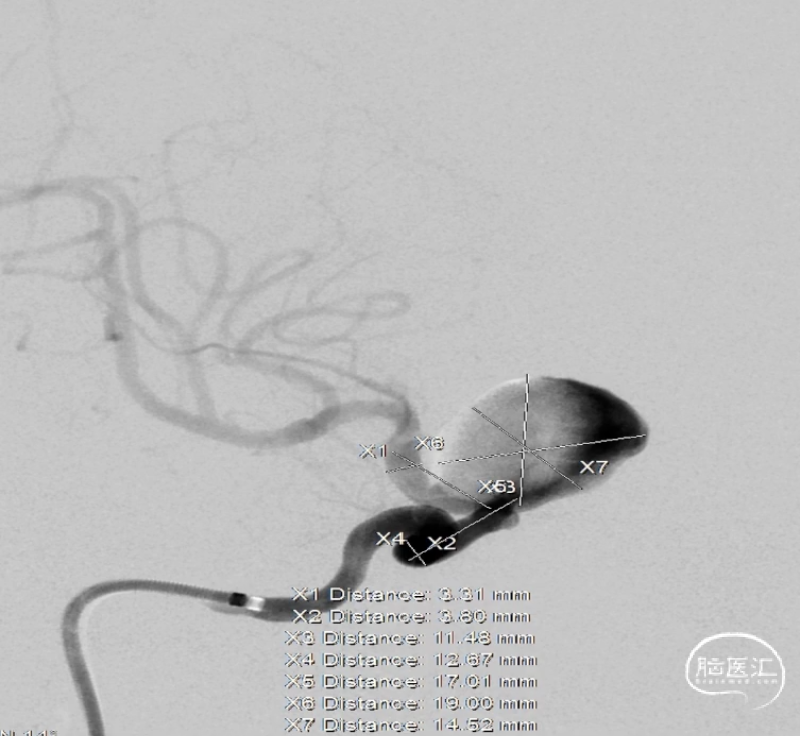

术前测量

动脉瘤:长:20.98mm;宽:17.13mm;高:19.08mm;典型颅内动脉大动脉瘤征。

载瘤动脉:瘤颈远端血管径:3.31mm,瘤颈近端血管径:3.80mm,瘤颈远近端长度:约24mm。